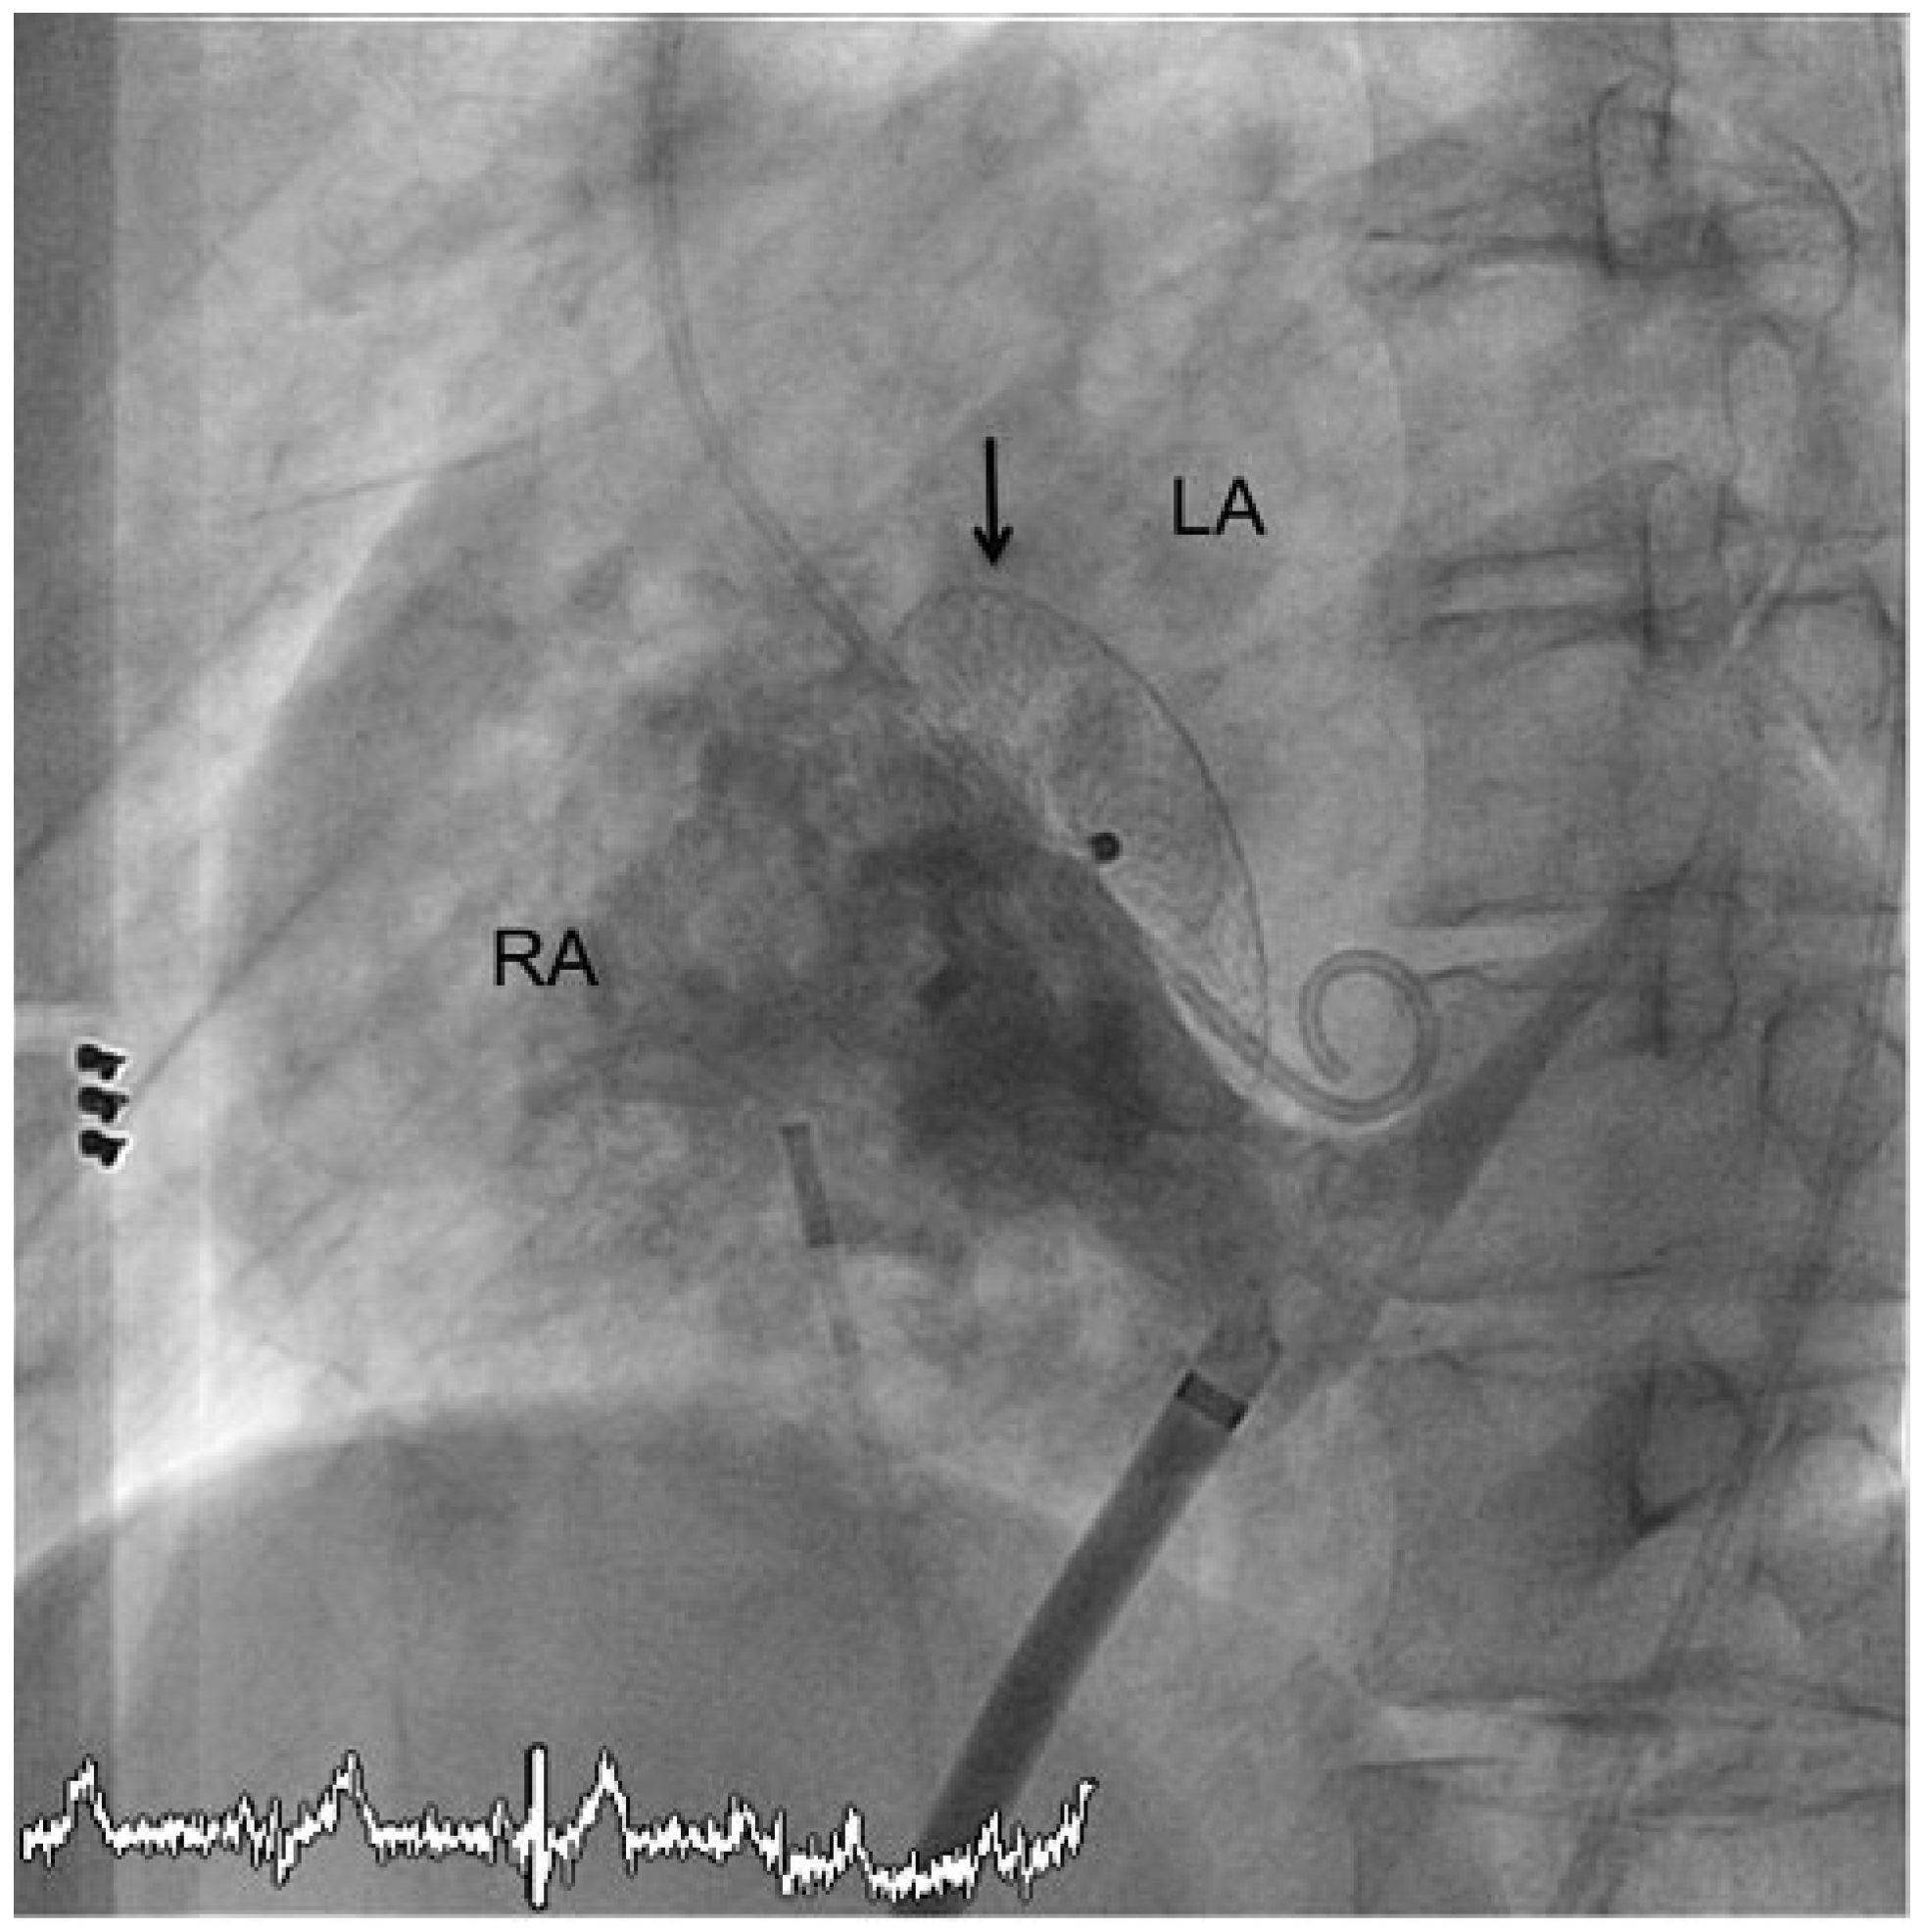

Percutaneous Implantation of an ASD Occluder with Intracardiac Ultrasound